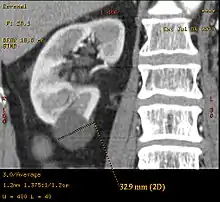

| کیست کلیوی کلیه در سمت چپ (ناحیه hyperintense) که در MRI نشان داده شدهاست. | |

تصاویر سیتیاسکن میتواند وجود کیست و تومور را در کلیه نشان دهد.[1]

تصاویر ام.آر. آی نیز مانند سیتیاسکن میتواند وجود کیست و تومور را در کلیه نشان دهد.[1]